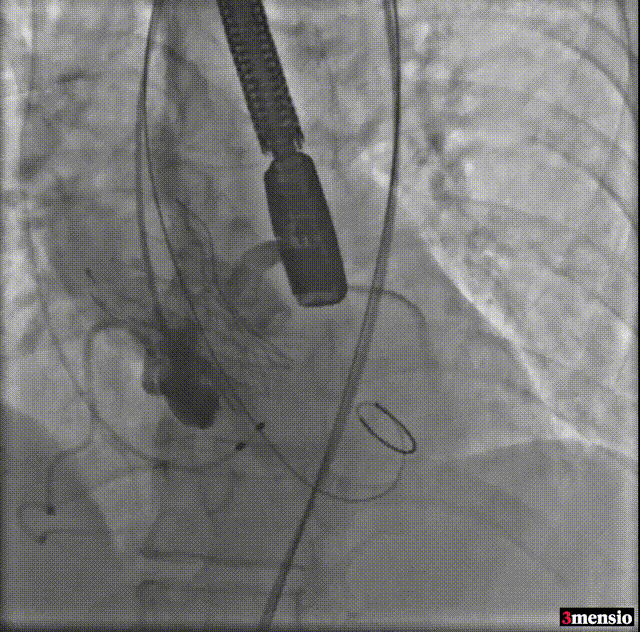

由于该病例瓣上限制较重,手术团队讨论决定使用沛嘉20mm球囊后扩处理:

球囊后扩

瓣膜最后形态造影

压差

术前压差:115mmHg

术后压差:9mmHg